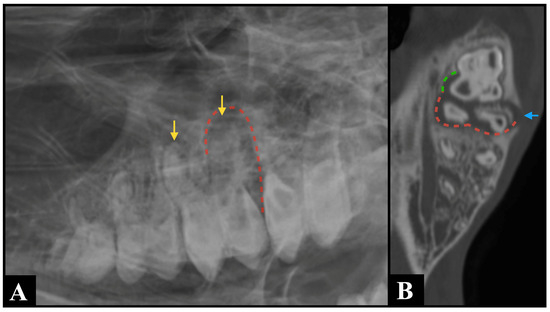

Odontogenic Cutaneous Fistula-Induced Submandibular Abscess in a Dog: A Rare Presentation

by Jong-Mu An, Won-Jong Lee, Dae-Hyun Kim, Seong Mok Jeong, Yoon-Ho Roh, Dongbin Lee and Chang-Hwan Moon

Vet. Sci. 2025, 12(11), 1071; https://doi.org/10.3390/vetsci12111071 - 7 Nov 2025

Odontogenic cutaneous fistulas (OCFs) are relatively uncommon in veterinary patients. They are typically caused by chronic periapical infections of the maxillary teeth. Mandibular OCFs that extend through the cortical bone into submandibular soft tissues are extremely rare. This report describes the case of [...] Read more.

Odontogenic cutaneous fistulas (OCFs) are relatively uncommon in veterinary patients. They are typically caused by chronic periapical infections of the maxillary teeth. Mandibular OCFs that extend through the cortical bone into submandibular soft tissues are extremely rare. This report describes the case of a 14-year-old male mixed-breed dog that presented with a submandibular cutaneous lesion initially misdiagnosed as a salivary mucocele. OCFs are frequently misdiagnosed because atypical presentations may lack obvious intraoral abnormalities and mimic salivary gland disease, lymphadenopathy, or cutaneous neoplasia. Computed tomography (CT) revealed a periapical lesion associated with the right mandibular first molar, cortical bone lysis, and extension into the adjacent submandibular tissues, which formed an external fistulous tract. Surgical management included extraction of the affected tooth, resection of the fistulous tract, and excision of the associated lymph nodes, which resulted in a complete and uneventful resolution of the fistula. At the 3-month follow-up, the patient remained clinically stable without evidence of recurrence. This case underscores the clinical pearl that odontogenic origins should always be considered in the differential diagnosis of submandibular or cervical cutaneous lesions and that cross-sectional imaging modalities, such as CT, are indispensable for confirming anatomical continuity and guiding surgical planning. Full article